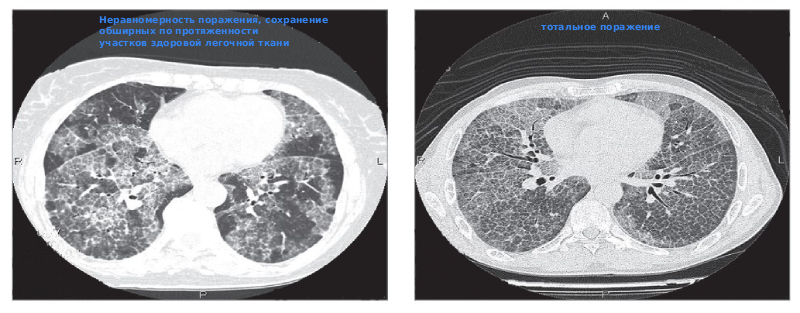

- Рентгенография грудной клетки – первый этап. На снимках обычно становятся видны «матовые стекла» – размытые затемнения в лёгких, чаще в нижних отделах.

- КТ: даёт более чёткую картину. Выявляет участки уплотнения с чёткими границами.